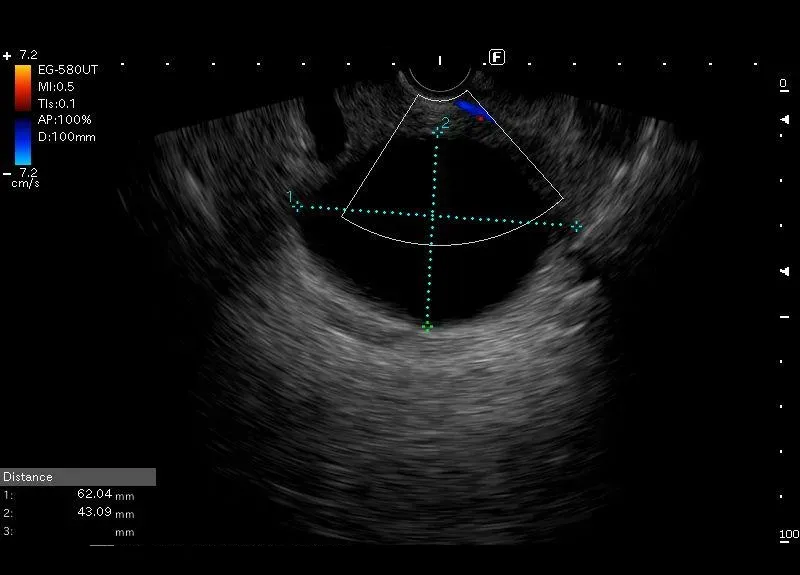

Owalna, bezechowa, cienkościenna zmiana o gładkich ścianach i wielkości 60/40 mm, bez widocznego przepływu w opcji power doppler, położona w wyrostku haczykowatym trzustki – obraz odpowiada torbieli trzustki.